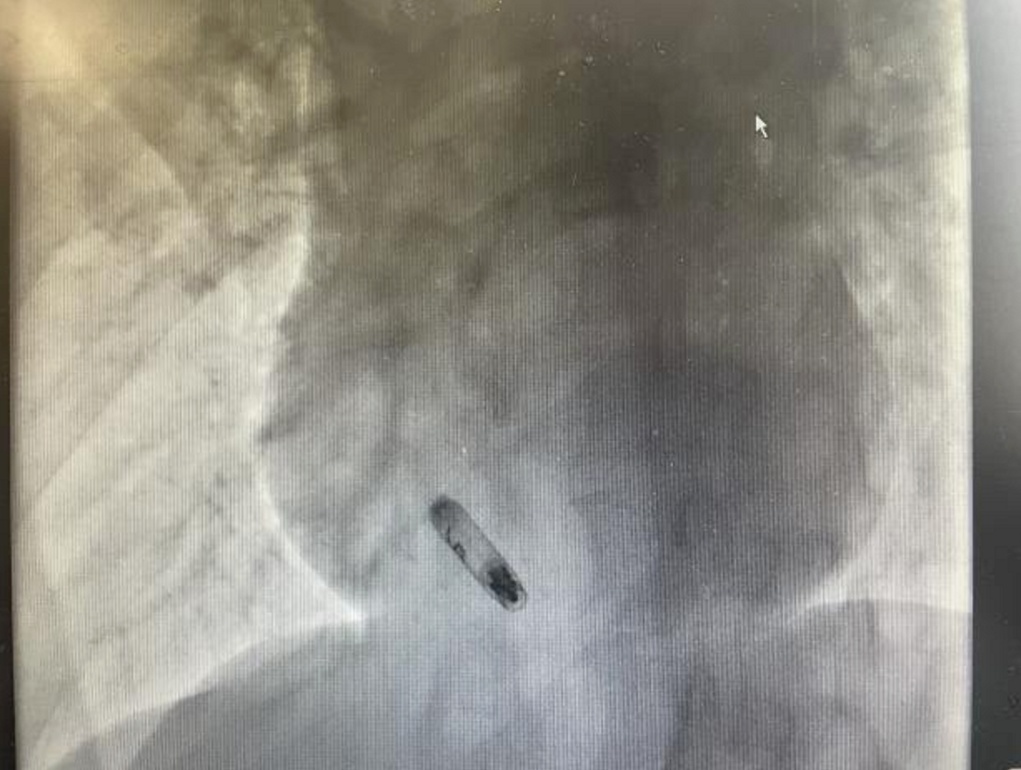

与传统的心脏起搏器治疗方式不同,无导线起搏器具有显著优势。传统治疗中,患者需要在体内植入一个脉冲发生器和多根电极,而无导线起搏器体积微小,仅有传统起搏器体积的十分之一,外形宛如一粒胶囊。它通过股静脉经导管置入心脏,操作简单且安全可靠。在此次手术中,从穿刺到释放仅用时40分钟,术程十分流畅,起搏器一次成功释放,郑女士在术中没有明显不适,术中术后电学参数均保持良好。由于无需建立囊袋且没有导线,该术式有效避免了囊袋感染的风险,减少了导线引发的三尖瓣反流等并发症,同时不会对患者肢体活动造成限制,大幅缩短了术后恢复时间。

术中,邱筱炜副主任医师团队严格按照标准植入流程进行操作,各项参数均符合要求,成功完成了手术植入。这一新技术为郑女士带来了诸多实实在在的益处。术中可实时监测参数,在旋入前标测电学参数,实现精准固定,显著降低了手术风险及心肌损伤的可能性。国外相关数据表明,约一半使用主动螺旋起搏器的患者使用寿命超过20年,这意味着郑女士后期更换起搏器的次数将大幅减少。而且,主动螺旋固定且配有专用取出鞘管的设计,使得起搏器电池耗竭后能够按需安全取出。此外,基于郑女士的疾病进展情况,未来还可按需升级为更加生理的真实双腔无导线起搏器,为她的健康提供了更长远、更全面的保障。